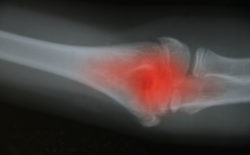

The Arthrex iBalance knee replacement system was designed to treat patients with multi-compartmental knee cartilage degeneration, which is often a result of osteoarthritis or post-traumatic arthrosis.

The Arthrex iBalance TKA Tibial Tray was recalled in December 2015 because the part was found to have a smooth texture when it was intended to have a rough texture.

The smooth texture was determined to be incompatible with the rest of the Arthrex iBalance Total Knee Arthroplasty (TKA) System, which was marketed as a superior product designed to reduce the need for more surgeries to remove metal components, including metal plates and screws.

In some cases, the Arthrex iBalance TKA Tibial Tray allegedly fails to properly bond, which doesn’t enable the knee replacement system to hold up under the stress of normal daily movement. Doctors report they have been able to pull the iBalance knee components apart by hand because of the failure of the Arthrex iBalance Tibial Tray to bond.

In a lawsuit against the device maker, plaintiff Mandy V. alleges that she received revision surgery had such a loose tibial tray that it fell out when the surgeon gently tugged on the part. Mandy had reportedly been in constant pain and suffered knee instability and hyperextension of the knee after she received the Arthex iBalance knee system in 2014. During the 2016 revision surgery, the surgeon was allegedly stunned that the components were so loose they nearly fell out without prompting.

She has since filed a lawsuit, which alleges, “A bone scan and x-rays showed clear evidence of component loosening and failure with constant increasing pain and discomfort with hyperextension and medial lateral instability.”